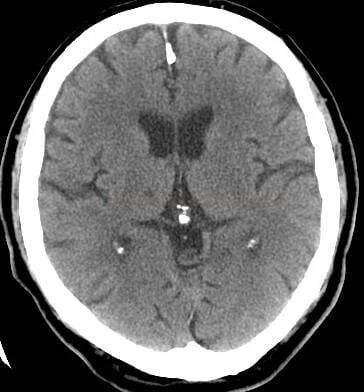

-_acp_1_perf_-_lakunarni_infarkt_v_thalamu_02_original

The thalamus (pl.: thalami; from Greek θάλαμος, "chamber") is a large mass of gray matter on the lateral wall of the third ventricle forming the dorsal part of the diencephalon (a division of the forebrain).

Thalamus je mozková struktura, která je součástí diencefala (mezimozek), a nachází se v blízkosti třetí mozkové komory. Má složitou strukturu, skládá se z řady jader a má komplexní funkce.

Thalamus – vejčitý útvar v diencefalu tvořící část stěny 3. mozkové komory. Přepojují se zde smyslové vjemy vč. bolesti vedené z periferie dále do mozkové kůry, z mozečku se do motorické kůry přepojují vzruchy důležité pro motoriku, další…

Thalamus (česky hrbol mezimozkový) je spolu s epithalamem součástí zadní části mezimozku (diencephalon) a je seskupením senzorických, asociačních a nespecifických jader. Zprostředkovává převod informací přicházejících z periférie do specifických projekčních a asociačních oblastí mozkové kůry a do důležitých center mozečku. Umožňuje také vzájemnou interakci vyšších oddílů CNS. Wikipedie